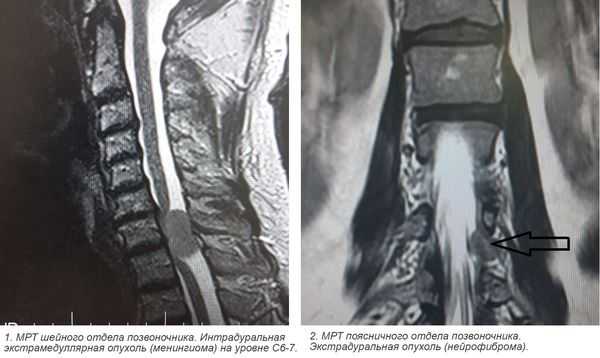

- экстрамедуллярные опухоли могут быть экстрадуральными (располагаются над твёрдой мозговой оболочкой) и интрадуральными, или субдуральными (локализуются под твёрдой мозговой оболочкой).

- менингиома (из клеток оболочек головного и спинного мозга);

- невринома (из клеток, образующих миелиновую оболочку нервов);

3. Магнитно-резонансная томография (МРТ) с контрастным усилением. На данный момент это основной метод диагностики новообразований спинного мозга. МРТ позволяет визуализировать весь спинной мозг и позвоночник и определить локализацию опухоли. Накопление контрастного вещества определяет не только распространение, но и гистологическую структуру опухоли [5] [6] .